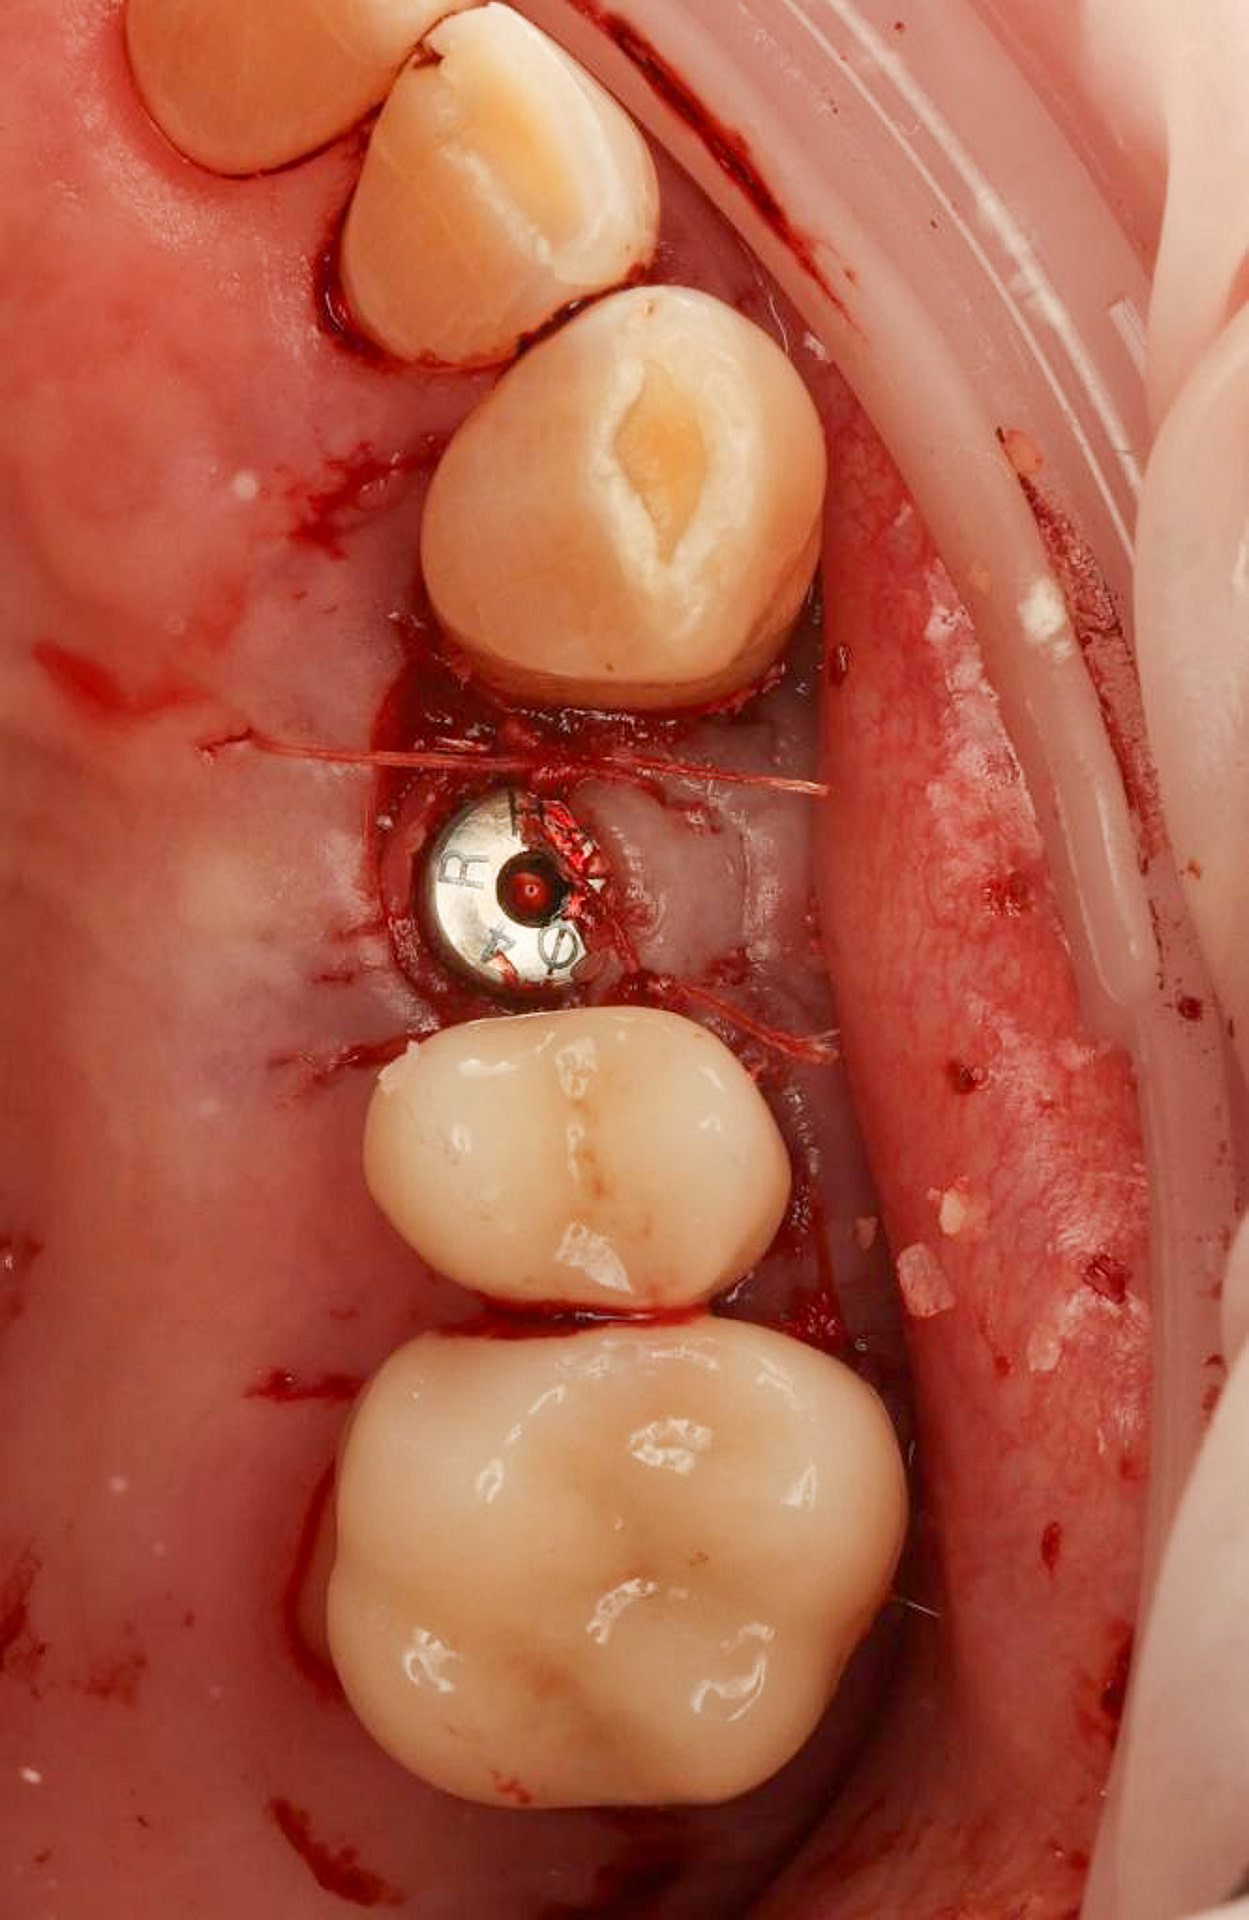

A custom surgical guide was designed and 3D printed, incorporating all the critical information from the virtual planning. The implant surgery was performed under local anesthesia, with the surgical guide firmly in place to ensure accurate implant placement. Bone grafting was performed to address the bony defect and promote optimal healing.

The Osstem OneGuide kit is used with a fully guided osteotomy and implant placement.

Osstem TSIII D4 x H10mm implant on NoMount driver.